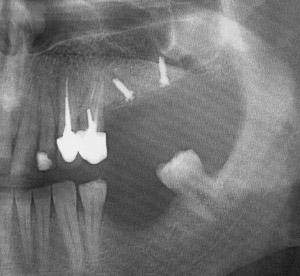

Greffe osseuse Ramique

L’os prélevé est rectiligne. Sa longueur peut atteindre ou dépasser 40 mm, sur une largeur de plus de 10 mm.

Ceci permet la pose de trois à quatre implants (réhabilitation d’un secteur latéral entier).